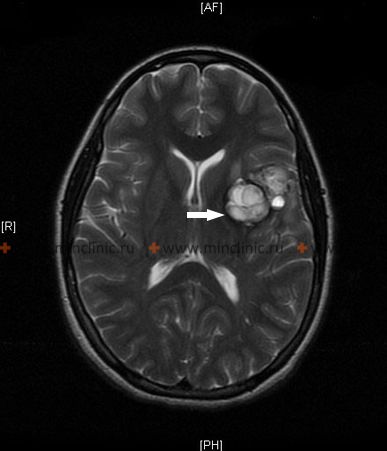

არტერიოვენოზური მალფორმაციები (ავმ) შედგება შეცვლილი სისხლძარღვების ნაწილებისაგან, რომლებიც ახდენენ არტერიული და ვენოზური სისტემების პათოლოგიური შეერთებების ფორმირებას. სინამდვილეში საუბარია არტერიოვენოზურ ანასტომოზზე ანდა ავმ, რომელიც თავის მხრივ განვითარების ანომალიაა. არტერიოვენოზული მალფორმაციისათვის დამახასიათებელია დროთა განმავლობაში იმ სისხლძარღვთა გაფართოება და დაგრძელება, რომლებიც შეადგენენ არტერიასა და ვენას შორის ამ ანასტომოზს.

არტერიოვენოზური მალფორმაციების ზომები მერყეობს რამდენიმე მილიმეტრის დიამეტრის ლაქიდან (რომლებიც მდებარეობს თავის ტვინის ქერქში ან თავის ტვინის თეთრ ნივთიერებაში) კლაკნილი არხების უზარმაზარ მასამდე, რომლებიც ქმნიან არტერიოვენოზურ შუნტს. ტვინის არტერიასა და ვენას შორის ეს შუნტი შეიძლება იყოს საკმაოდ მნიშვნელოვანი გულის გამოყოფილი სისხლის გაფართოებისათვის. ტვინის ჰიპერტროფული და გაფართოებული არტერიული "მკვებავი" სისხლძარღვები აღწევენ დაზიანების ძირითად ზონამდე, ქრებიან თავის ტვინის ქერქის ქვეშ და იშლებიან თხელკედლიანი სისხლძარღვების ქსელად. შემდეგ ეს სისხლძარღვოვანი ქსელი ტვინის ვენებით უშუალოდ უერთდება დრენირებად არტერიოვენოზურ მალფორმაციებს. ისინი ხშირად ქმნიან გიგანტურ, გაფართოებულ, პულსირებად არხებს, რომლებსაც გამოაქვთ არტერიულ სისხლი.

არტერიოვენოზური მალფორმაციების წნულის წარმომქმნელი სისხლძარღვები, რომლებიც არტერიებსა და ვენებს შორისაა განლაგებული, როგორც წესი, პათოლოგიურად შთხელებულია და მათ არა აქვთ არტერიებისა და ვენების ნორმალური სტრუქტურა.

ავმ თავის ტვინის, ტვინის ღეროსა და ზურგის ტვინის ყველა ნაწილში შეიძლება შეგვხვდეს, მაგრამ მათგან ყველაზე მსხვილები უფრო ხშირად ნახევარსფეროს უკანა ნაწილებშია განლაგებული სოლისებრი დაზიანებების ფორმით, რომლებიც ვრცელდებიან ქერქიდან პარკუჭოვანი სისტემისაკენ.

არტერიოვენოზური მალფორმაციების ვიზუალიზაციისათვის, მათი მდებარეობისა და ზომების განსასაზღვრად გამოიყენება თავის ტვინის სისხლძარღვების მაგნიტურ–რეზონანსული და კომპიუტერული ტომოგრაფიები (ანგიოგრაფიის რეჟიმი) კონტრასტული ნივთიერებების გამოყენებით. მაგნიტურ–რეზონანსული და კომპიუტერული ტომოგრაფიები (ანგიოგრაფია) შესაძლებლობას იძლევა გამოვლინდეს არტერიოვენოზური მალფორმაციების არხები მათ გასკდომამდე.